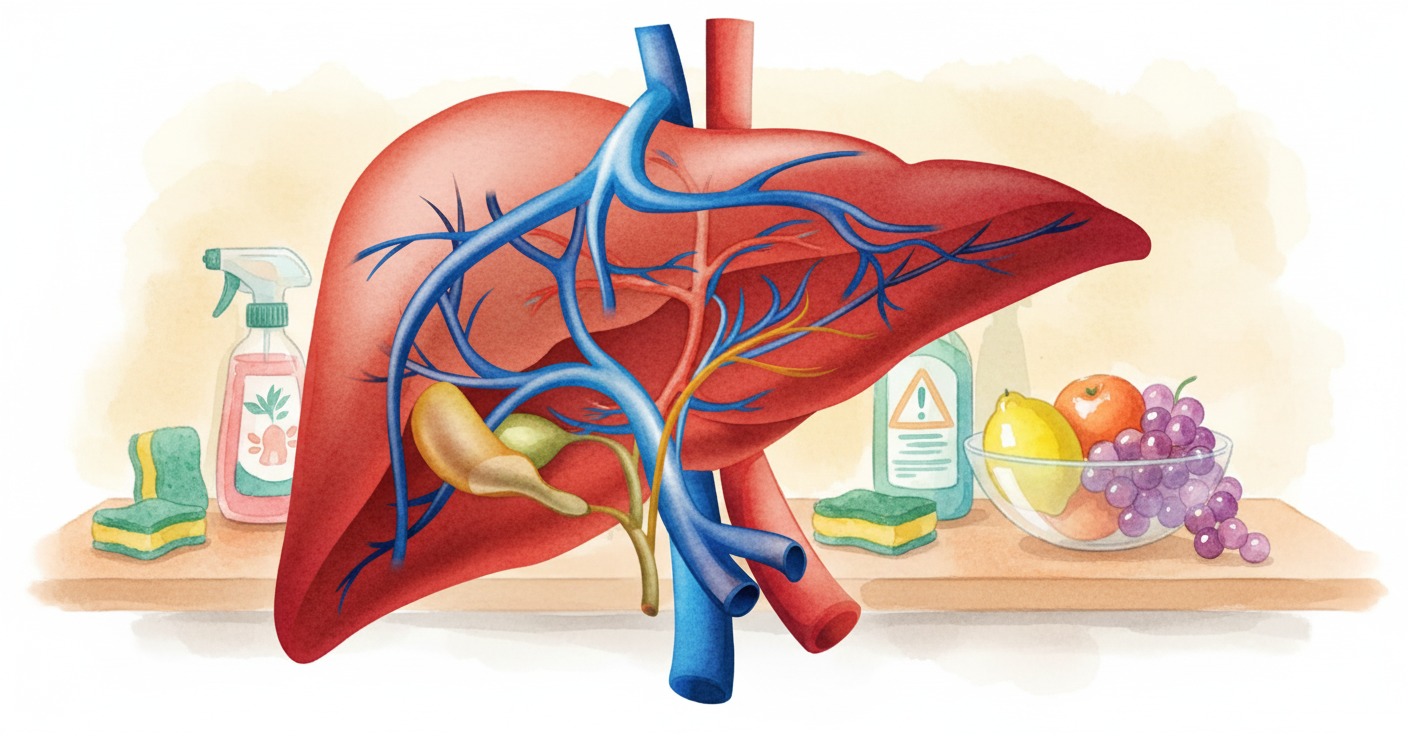

La exposición prolongada al tetracloroetileno (PCE), un químico común en la limpieza en seco y desengrasantes, puede triplicar el riesgo de desarrollar fibrosis hepática significativa, según un estudio de Keck Medicine of USC. La investigación revela que el 7% de los adultos analizados presentaba niveles detectables de la sustancia en sangre.

El peligro en el hogar y en el entorno laboral podría no ser siempre visible. Investigadores de Keck Medicine of USC han alertado sobre la relación entre un producto químico de limpieza común y el deterioro del Hígado. La exposición al tetracloroetileno (PCE), también conocido como perc y usado en la limpieza en seco, se asocia con un riesgo hasta triplicado de desarrollar fibrosis hepática significativa.

El estudio, publicado en Liver International, es una de las investigaciones más sólidas en vincular la contaminación doméstica y ocupacional con el daño progresivo de este órgano. Además, reveló que alrededor del 7% de los adultos analizados en la muestra tenían niveles detectables de PCE en su sangre.

El tetracloroetileno (PCE) es un compuesto orgánico volátil. Se utiliza ampliamente en adhesivos, removedores de manchas, pulidores y en equipos de limpieza en seco. El solvente puede liberarse de prendas recién lavadas o mediante su acumulación en agua y aire. La novedad radica en que, hasta ahora, el foco se había puesto en sus efectos neurológicos o reproductivos. Rara vez se había vinculado con Enfermedades del Hígado de forma tan directa.

La investigación revela que incluso bajos niveles de PCE en el organismo pueden causar daño. El PCE, una vez metabolizado en el Hígado, genera metabolitos tóxicos. Estos subproductos químicos dañan las membranas celulares, desencadenando inflamación y favoreciendo la formación de tejido cicatricial. Así, la lesión no es instantánea, sino progresiva y silenciosa. El hígado acumula daño hasta que la fibrosis se vuelve significativa. Esta condición puede evolucionar a cirrosis, fallo hepático o cáncer.

El equipo liderado por el hepatólogo Brian P. Lee halló un dato más preocupante. Por cada aumento de un nanogramo por mililitro en sangre de PCE, las probabilidades de fibrosis se multiplicaban por cinco. Sorprendentemente, estos efectos se mantuvieron incluso después de ajustar el análisis por consumo de alcohol, obesidad o diabetes. Estos son factores tradicionales de riesgo hepático. Ello sugiere que la exposición química es un actor independiente en el daño al Hígado.